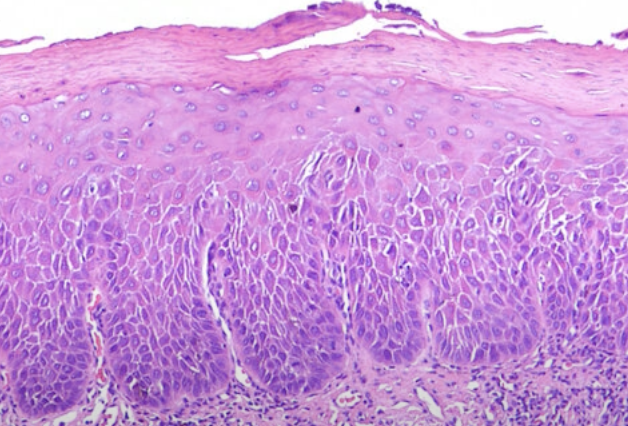

Oral epithelial dysplasia (OED)

- 分為三個程度

Mild

- 影響到下三分之一

- Basal cell 增生,變大

- Rete ridge 變寬

- 底層 keratin (紅染)

- 可能發炎